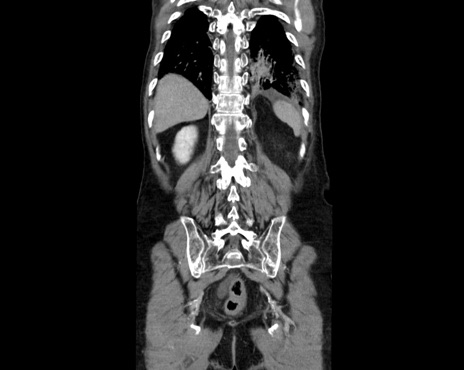

横断像

【症例】80歳代男性

【主訴】嘔吐

【現病歴】昨晩2回嘔吐あり、今朝になっても嘔吐あり。来院。

【既往歴】胃潰瘍

【身体所見】意識清明、BT 37.6℃、BP 166/95mmHg、HR 100bpm、SpO2 97%、腹部:平坦・軟、腸蠕動音聴取良好、圧痛なし。

【データ】WBC 21900、CRP 1.4